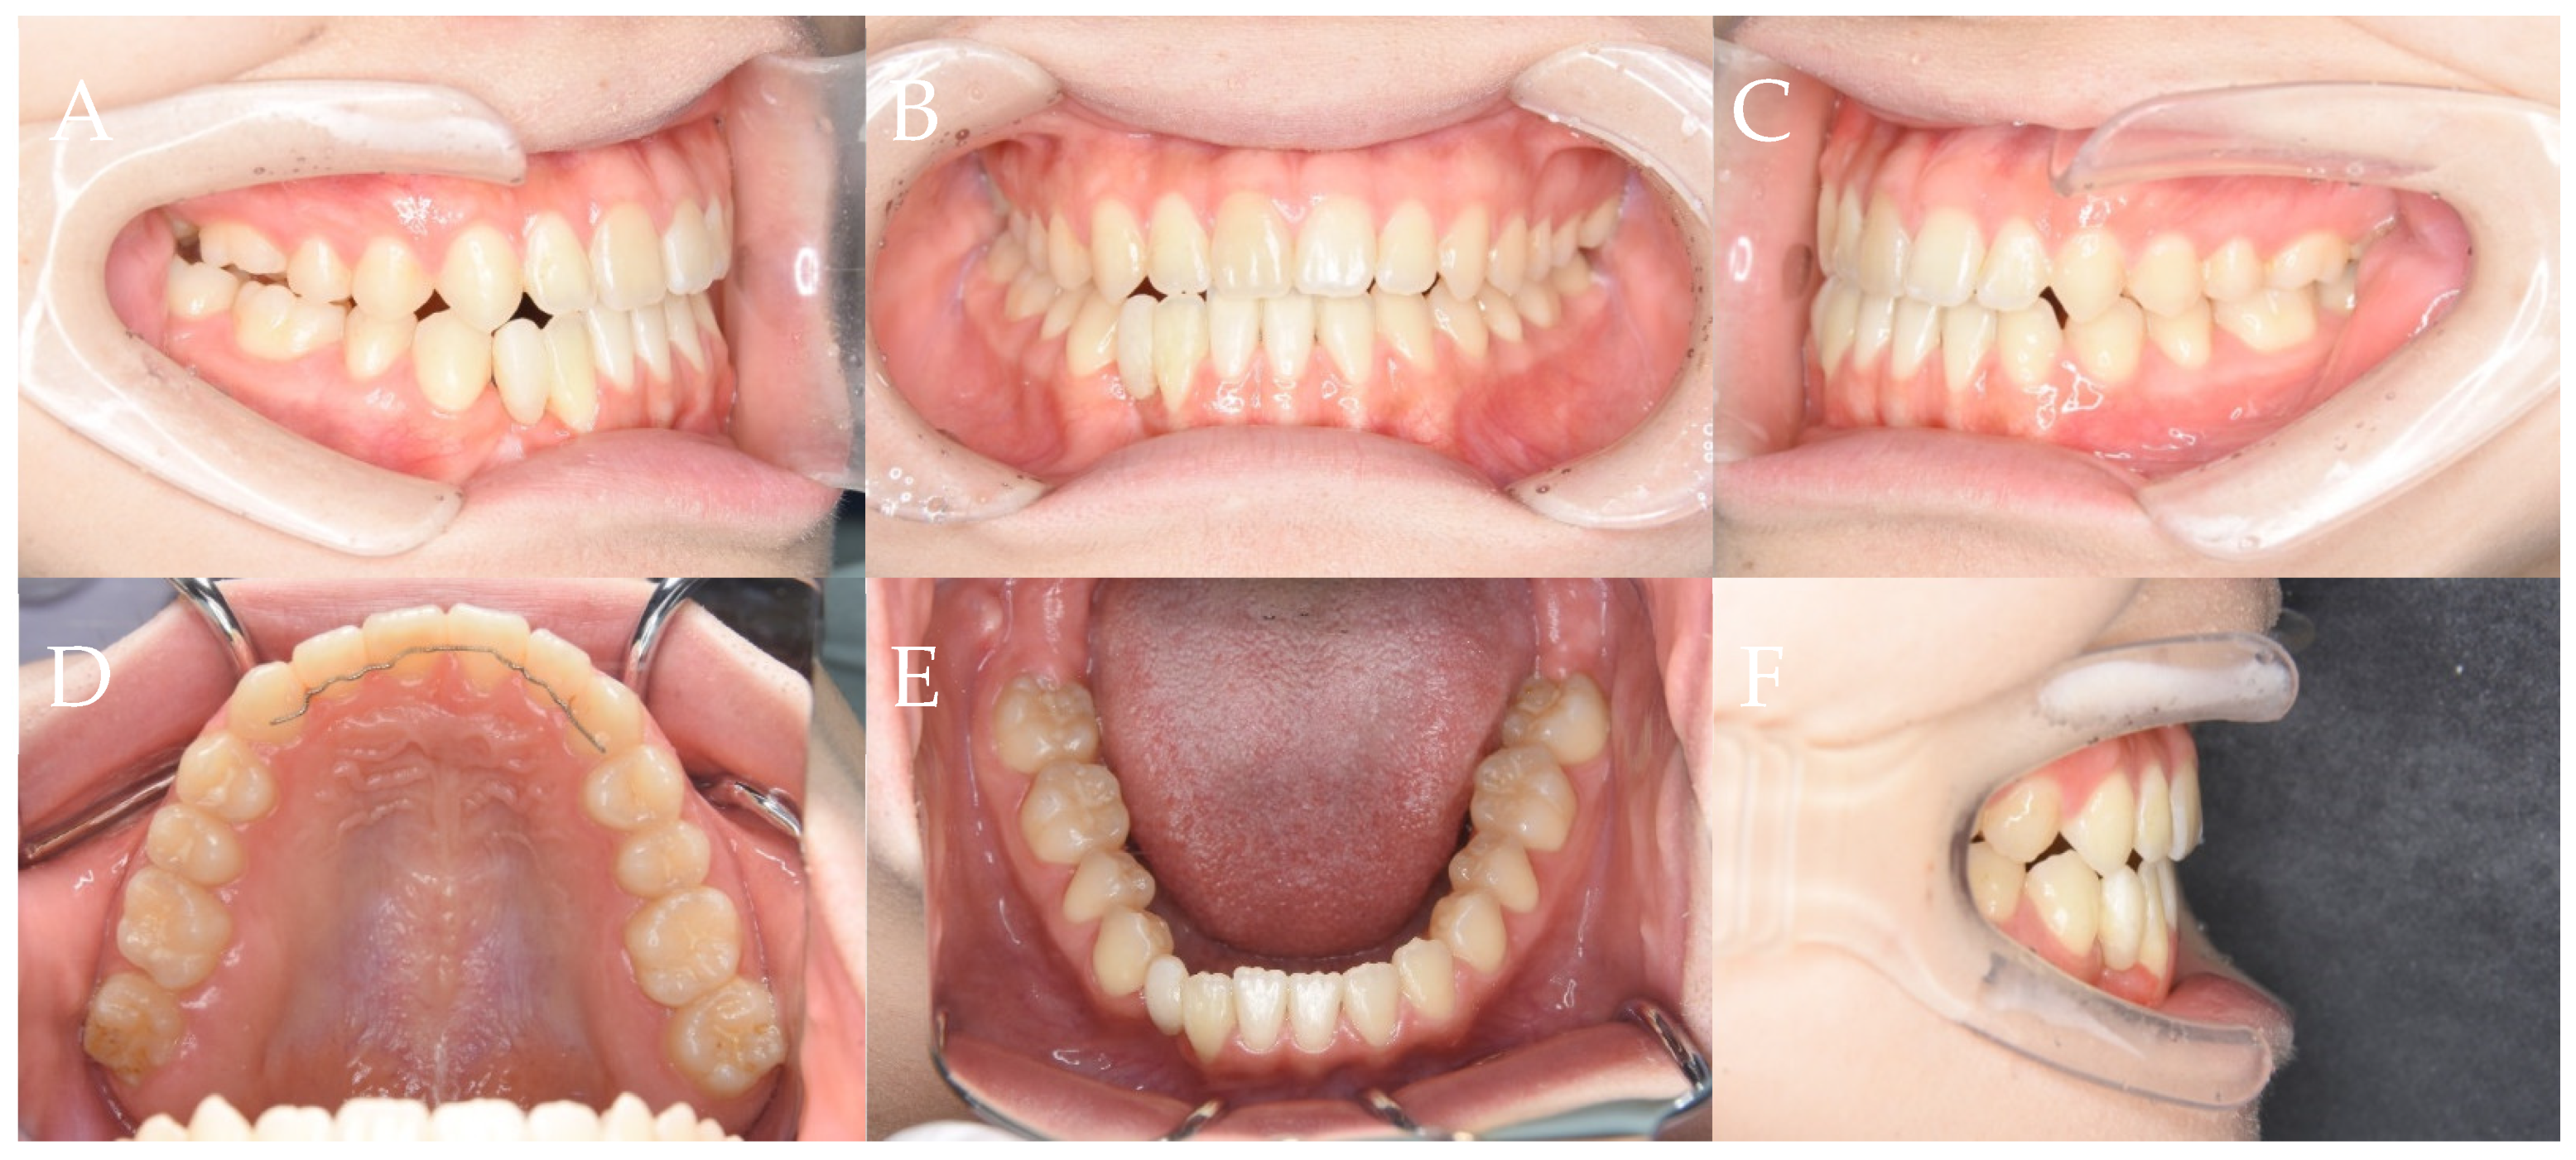

2.5. Clinical Examination

2.6. Imaging Examinations

2.7. Diagnosis